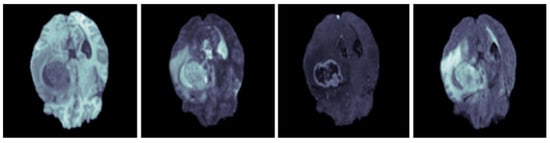

259 glioma images of higher grade and 76 lower grade images are included in the BraTS 2019 data, the manual creation of a ground truth by the expert neuroradiologists is utilized for the annotation protocol. In the database, the MRI scans belong to 4 modalities, such as T1, T2, T2-CE, and T2-FLAIR, and example scans are given in Figure 4.

Figure 4.

Sample MRI brain scans of BraTS 2019 database [36].